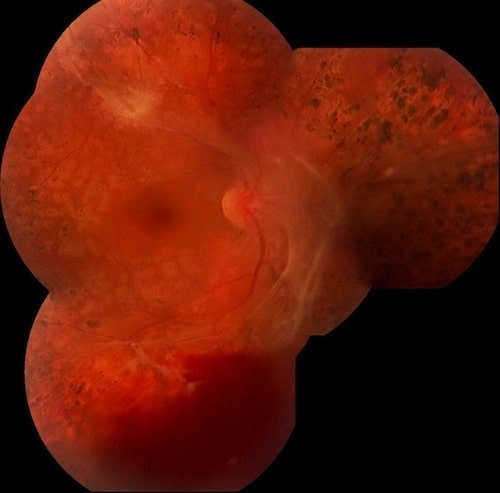

Retinopatia diabetica proliferativa.

Un año mas tarde post vitrectomia y endolaser.